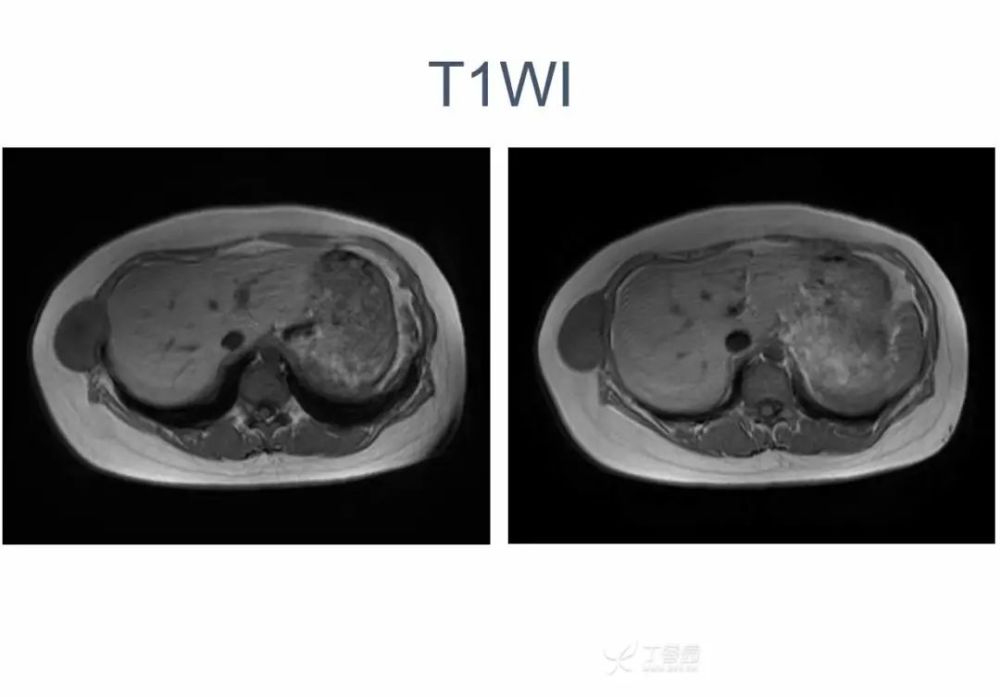

女,22 岁。右下侧胸壁疼痛、不适 10 年,近 3 年发现右侧腋中线近肋弓处肿块。体检:局部皮肤无红肿,肿块质中等偏硬,活动度欠佳,压痛( + ),无血管杂音。超声描述「低回声包块」。化验室指标无异常。